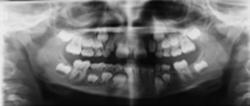

Dental pantomograms of the early mixed dentitions for evaluating mainly the primary dentition

Two phenotypically different groups of resorption were identified according toBille et al. (2007). Eight children (four boys and four girls) belonged to group I (Figure 1) and four children (three boys and one girl) to group II (Figure 2).

Figure 1

Dental pantomogram of a girl aged 6 years 4 months in the early mixed dentition with unexpected early apical resorption. Invaginations of the permanent maxillary lateral incisors, short roots of the permanent maxillary central incisors, and agenesis of the left permanent mandibular second premolar are seen. A follow-up radiograph (not shown) taken 2 years 8 months later confirmed findings of dental deviations seen on the first radiograph, but did not provide any additional findings of dental deviations in the permanent dentition.